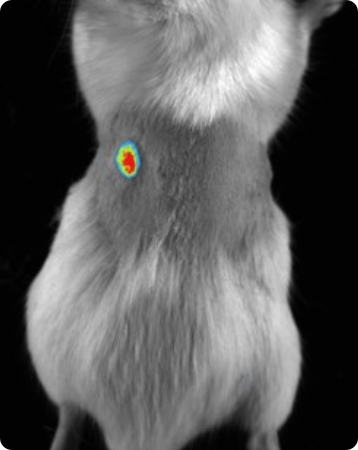

Fluorescence imaging

Vilber's dynamic range of emission filters can be employed in fluorescence imaging to identify fluorescent reporter genes or dyes in vivo.

Subcutaneous tumor expressing mCherry. Image Credit: Scintica Instrumentation Inc